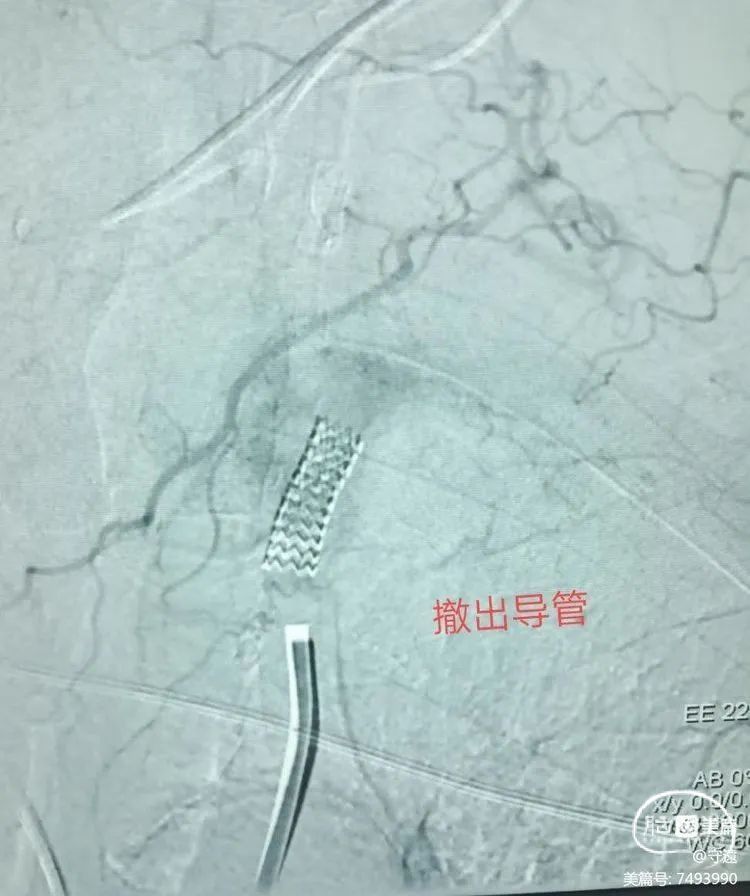

将球囊完全泄压后支架置入。

造影显示支架位置良好,狭窄解除,左侧椎动脉恢复正向血流。

右侧椎动脉造影显示:左侧椎动脉逆向血流消失。双侧椎动脉血流恢复正向。